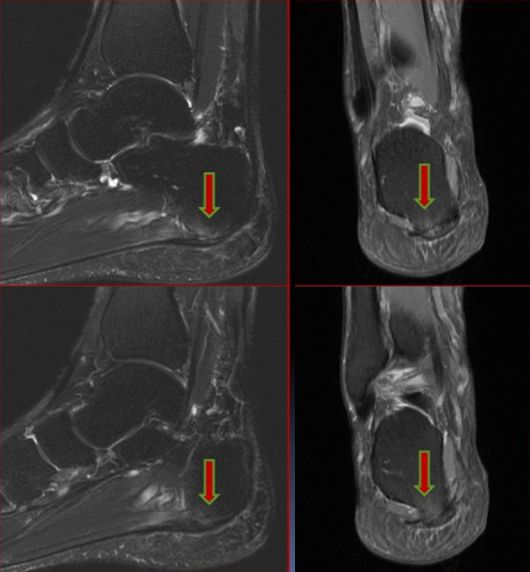

五、三角骨综合症

三角骨是距骨后端二次化中心,由软骨桥相连接。

病因:距骨三角骨急性骨折或慢性应力性骨折,胫骨后部或附近肌腱韧带反复撞击、压迫三角骨,引起踝关节囊后部级相邻的韧带和拇长屈肌腱的炎症。

MRI显示三角骨内骨髓水肿,邻近关节囊积液,软组织水肿级炎症,拇长屈肌腱水肿、腱鞘积液。